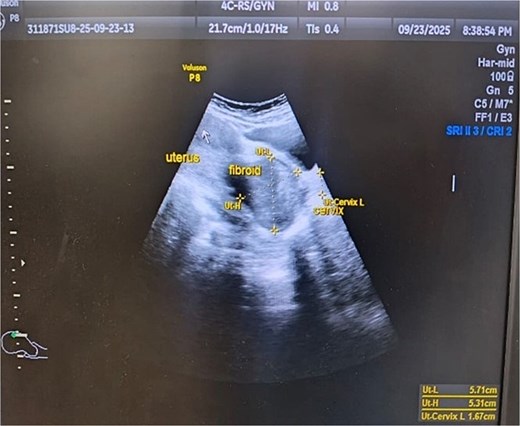

A 43-year-old, married woman, para 3 living 3, presented with a mass coming out from the vagina and gradually increasing in size for 1 year. She also had complaints of offensive vaginal discharge and irregular vaginal bleeding for last 3 months, with passage of clots and intermenstrual spotting. The mass was irreducible in nature, this ruled out differential diagnosis of uterovaginal prolapse. There were no associated bladder or bowel complaints. She had no significant medical or surgical history. She has never used any hormonal therapy. Her last menstrual period was 2 weeks ago. On general examination, she had moderate pallor. A 6 × 6 cm necrotic, irregular, lobulated mass protruding outside the introitus and had variable consistency, varying from soft to firm with some friable areas. These clinical findings raised the suspicion of malignancy. Ultrasound examination showed an anteverted uterus of 8 × 5.5 × 4.3 cm and thin endometrium shown in Fig. 5. Both ovaries were unremarkable. Cervical fibroid of size 5.7 × 5.3 cm was seen on sonography. The patient was transfused with 2 units of packed red cells and worked up for examination under anesthesia and biopsy. Intraoperative findings showed an anteverted uterus of 10 weeks size with a large, grossly necrotic mass of 6 × 6 cm was seen extruding through a healthy-looking cervix by ~2 cm long and 2 cm thick stalk arising from posterior wall of cervix and protruding into the vagina and outside the introitus i.e. Fig. 6. A provisional diagnosis of cervical fibroid polyp was made. Pedicle of fibroid polyp was held with the clamp, cut, and transfixed with vicryl-1 suture. Endometrial curettage and cervical biopsy were done. Intraoperative bleeding was managed with cautery and vaginal packing. She received postoperative analgesics and antibiotics. Post-operative hemoglobin was 9.1 gm/dl. Patient’s postoperative period was uneventful. Patient was discharged on postoperative day 2 with advice to review with histopathology report. The histopathological result of the mass confirmed a benign leiomyomatous polyp of cervical origin. Cervical biopsy and endometrial curettage showed no malignant changes or atypia.

Ultrasonographic image of fibroid polyp of size 5.71 cm × 5.31 cm.